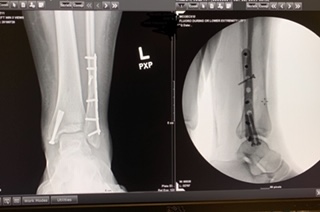

On May 25, 2010, I survived a head-on collision on Route-87. An 89-year-old man with dementia crossed over the meridian and hit me head on. After paramedics took 1 1/2 hours to free me from the vehicle, I was air lifted to a facility in Westchester, who wanted to amputate my lower right leg. At this facility, I had 2 surgeries there to "clean out" the right tibia and leg. My ankle was crushed from the accident. When I was there, I called my friend to help me. My friend, who used to be a PA at HSS, recommended me to Dr. Helfet, who eventually saved my leg after 3 surgeries. I consider him to be the Guru of orthopedic surgeons. Six months after the surgeries, I was back in high heels. Soon after that, I could hike mountains. If it was not for Dr. Helfet and HSS, I would not be where I am today.